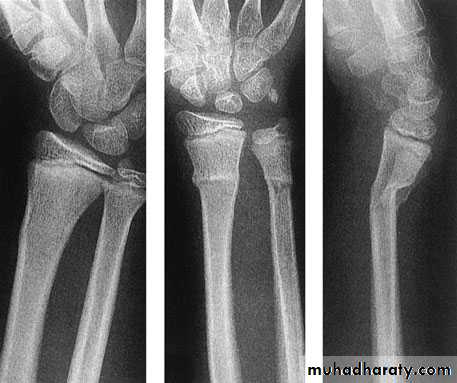

The commonest fragility fractures:

Colles fracture

Femoral neck fracture

Thoracic and lumbar vertebrae fractures